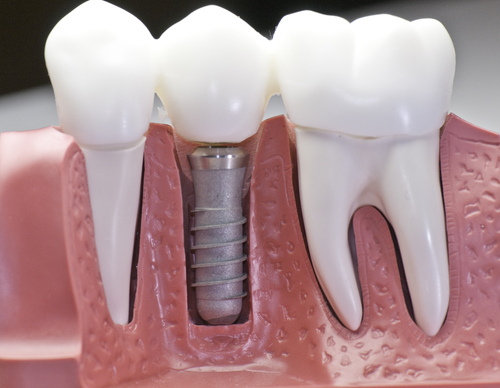

インプラント

歯がない部分にチタンのネジを埋め込み、それに被せ物をいれる方法です。歯がないと年齢より歳をとってみえたり、話しにくいなどの弊害がありますが、それらを改善します。歯がない部分にはインプラントの他にブリッジや入れ歯という選択肢もあります。

麻布十番の歯医者さんで使用するインプラントの模型のイメージ